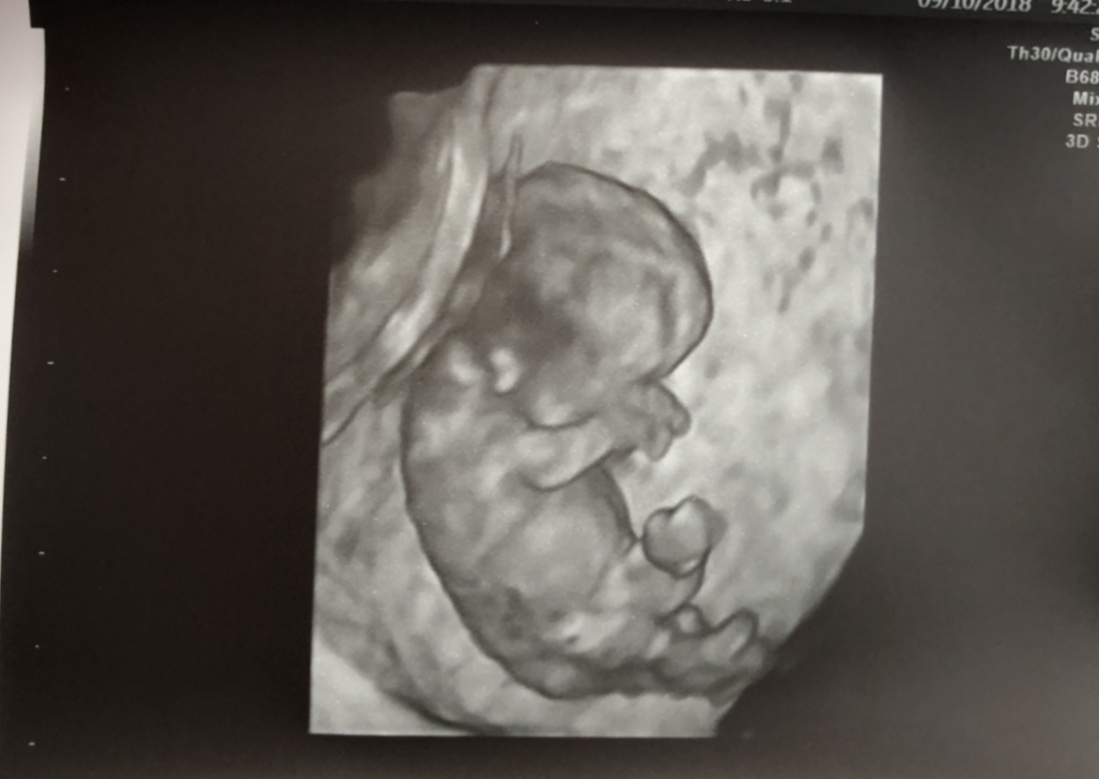

Any recent / upcoming appointments? Had my weekly appt yesterday. Our u/s tech always pops it into 3D and I just can't believe it - we could see his ears, his little arms were covering his face already. Like guys - they look like babies already!! I can't believe it.

Editing to add one of our 3D pictures because I literally can’t stop looking. I can’t believe how he’s looking already